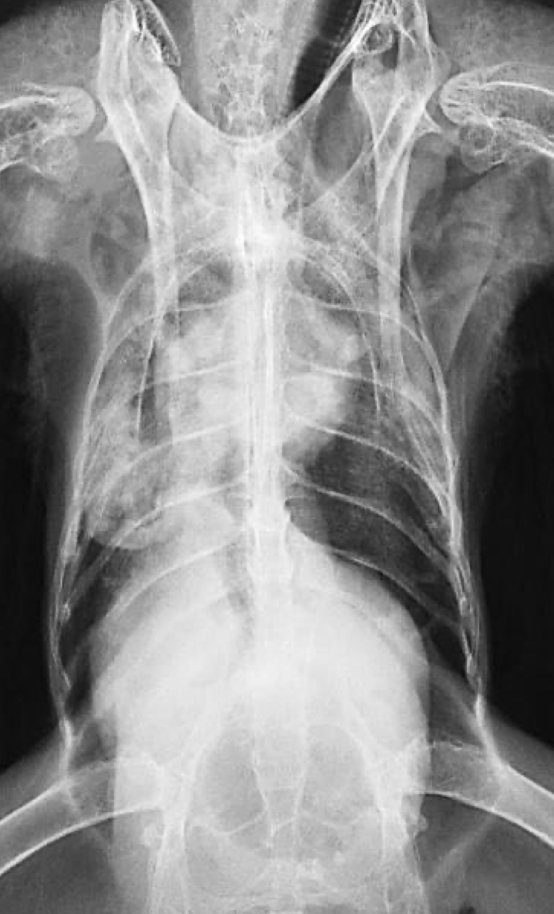

Correct radiograph positioning VD

Normal avian body xray